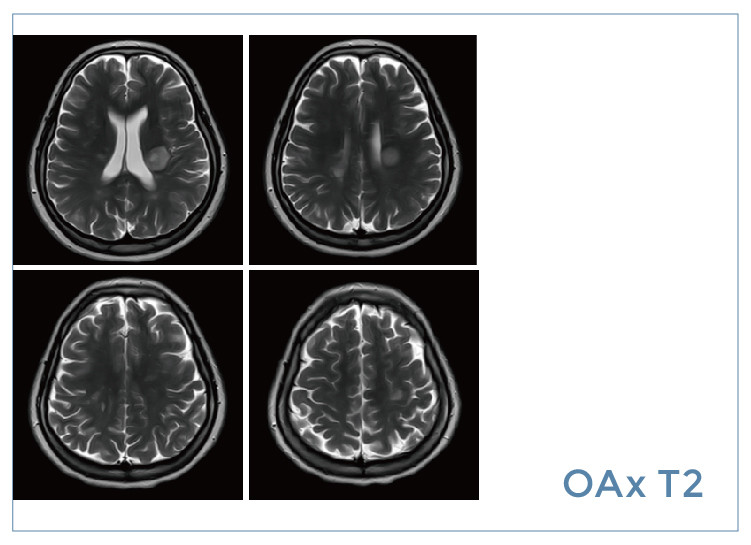

【朗润影像档案】磁共振影像病例分享(编号20190823)